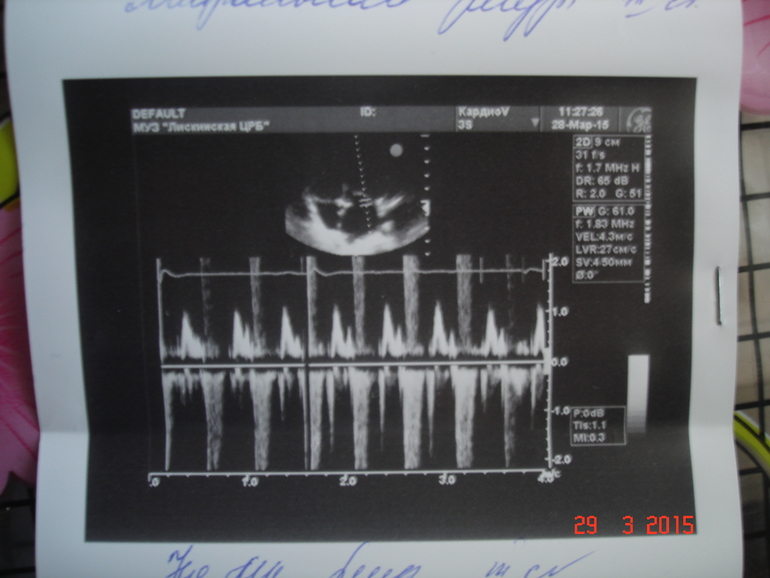

Здравствуйте! Выявлена недостаточность митрального клапана с регургитацией 3 ст (самая высокая степень регургитации, т.е. обратного тока крови через клапан), есть уже осложнение — расширение левого предсердия. Левый желудочек на сегодняшний момент адекватно работает, полностью справляется со своей функцией, сократимость его не нарушена. Поэтому, вероятнее всего, кроме шума в сердце, клинических проявлений нет. Вам обязательно нужно показаться детскому кардиологу, вероятно, назначат медикаментозное лечение. В более старшем возрасте (и в зависимости от дальнейшего развития событий) - консультация кардиохирурга.